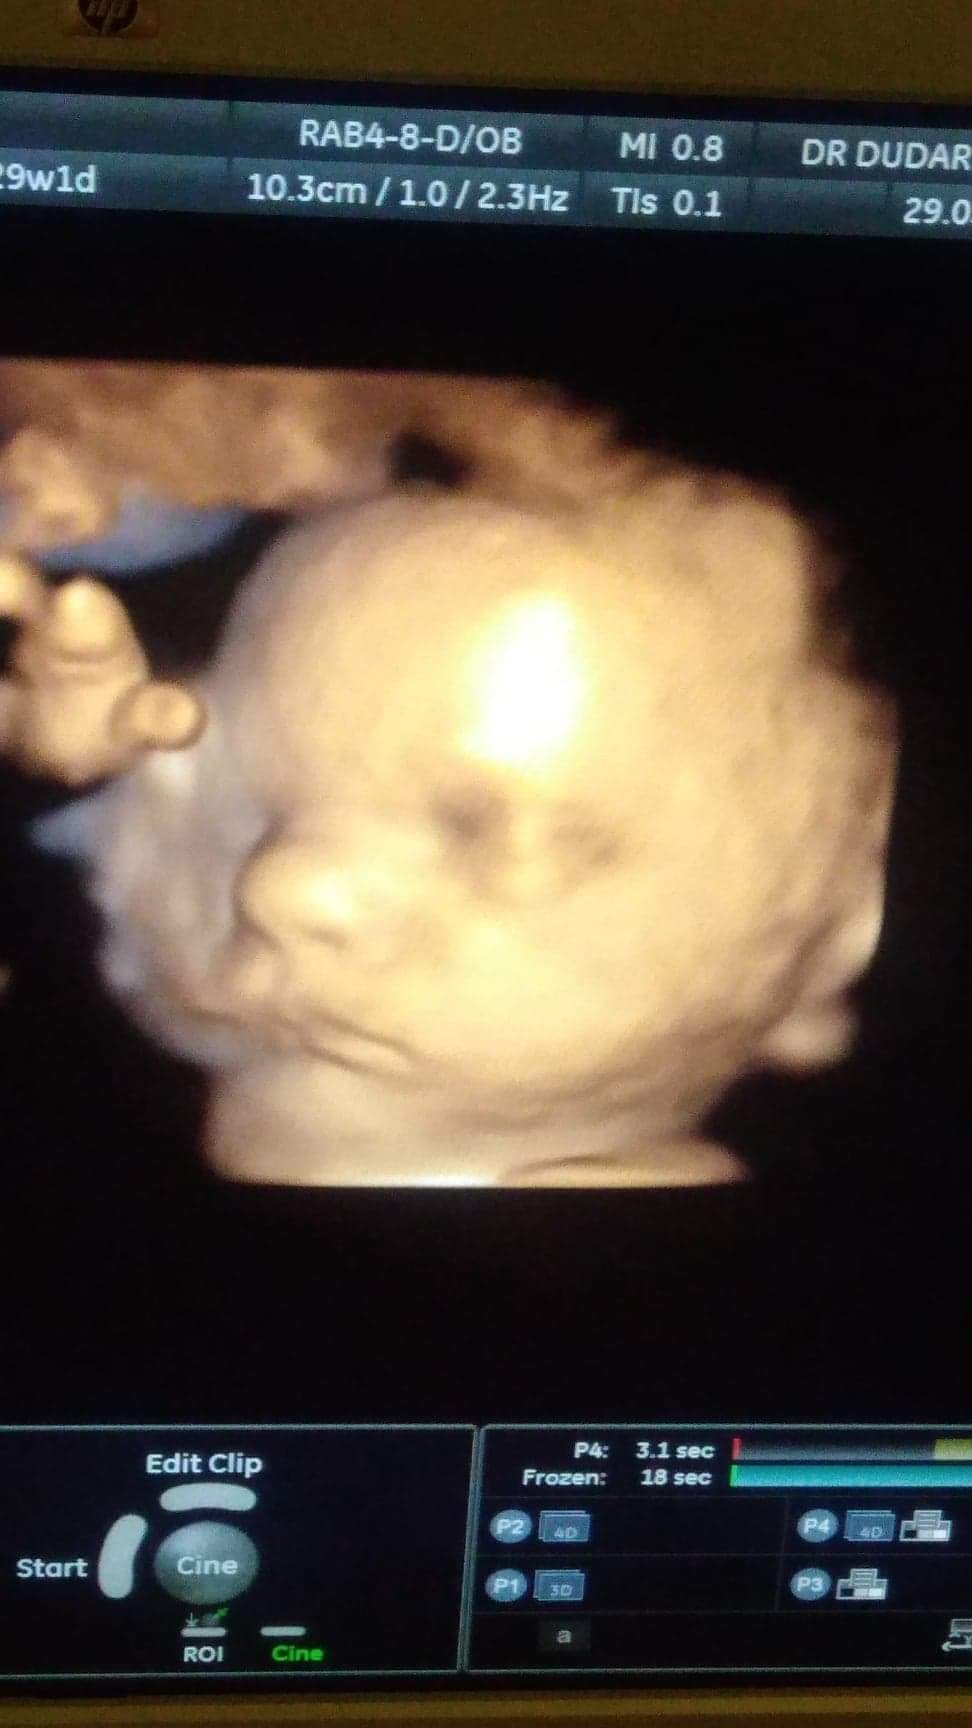

Ciąża po 40

Hej kobietki [emoji16] miałam dziś USG trzeciego trymestru u tego doktora Dudarewicza w Łodzi i nie uwierzycie .... Nie ma śladu po łożysku przodującym [emoji16][emoji3] jeszcze jestem w szoku. Synek leży główka do dołu centralnie na szyjce a szyjka ma ...uwaga : 4, 86 cm[emoji849]hehe także cesarki nie będzie, uff. Dziś jest 29+2 a wg USG 31+4. Waga 1698, wiadomo mniej więcej.Ten lekarz jest super, wszystko posprawdzal, każda żyłkę tetnice widać było. Przepływy po dwa razy . Dzidziulek zdrowiutki[emoji3][emoji8][emoji7] bardzo ładnie współpracował a samo badanie trwało ponad pół godziny. Ciekawe co powie mój prowadzący w poniedziałek (nie przyznam się że bylam na tym badaniu bo wg niego jest niepotrzebne) i czy zauważy różnice w położeniu łożyska. A to mój synek ( ze zdjęcia cały tatuś [emoji8])Zobacz załącznik 957332Zobacz załącznik 957333